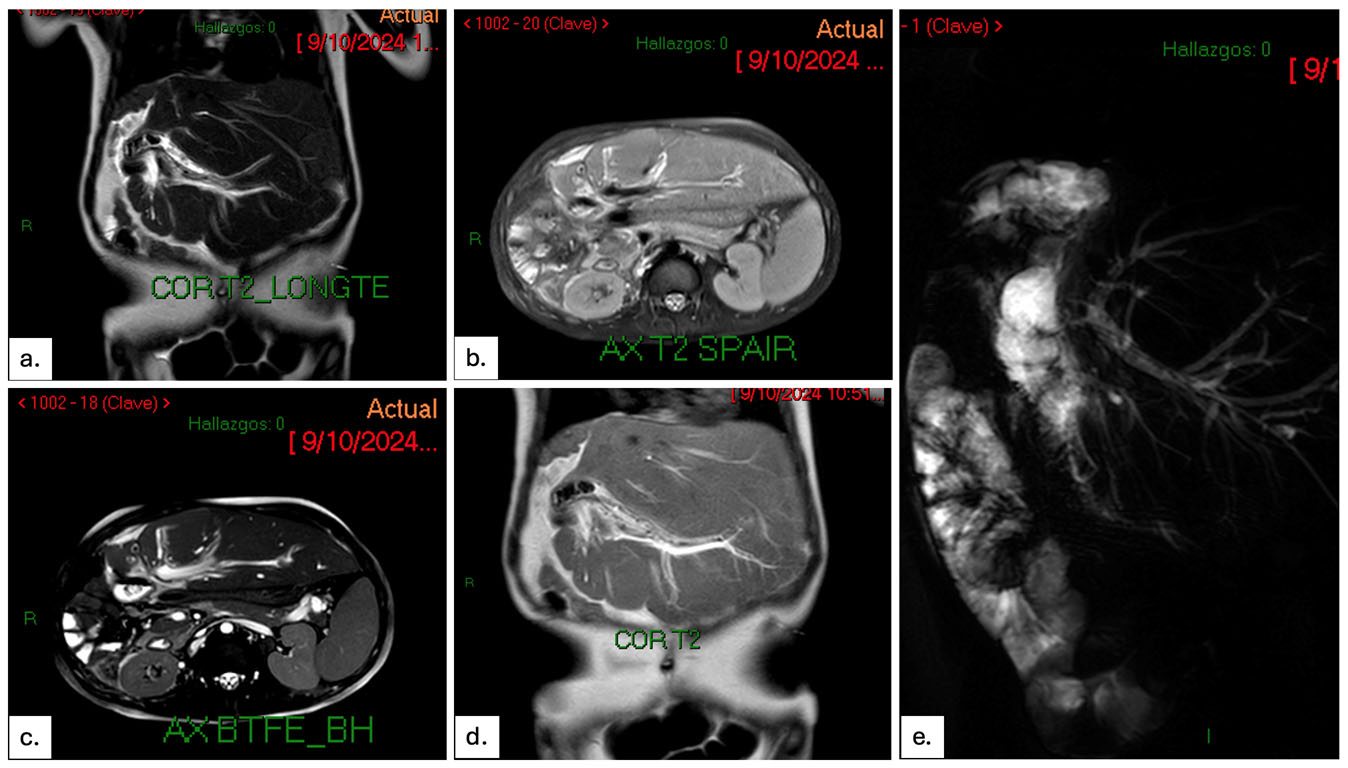

Resonancia magnética abdominal 3T con contraste

En los cortes de resonancia magnética contrastada, ¿cuál es el hallazgo predominante?

VERDADERO (en este caso)

Se demuestra dilatación de la vía biliar intrahepática y defectos de llenado en su interior, además de edema periportal sugestivo de colangitis. En la secuencia colangiográfica 3D (e) se demuestra la dilatación de las vías biliares intrahepáticas con defectos de llenado en su interior. No hay trombos ocupando la porta ni cambios en la intensidad del parénquima pancreático.